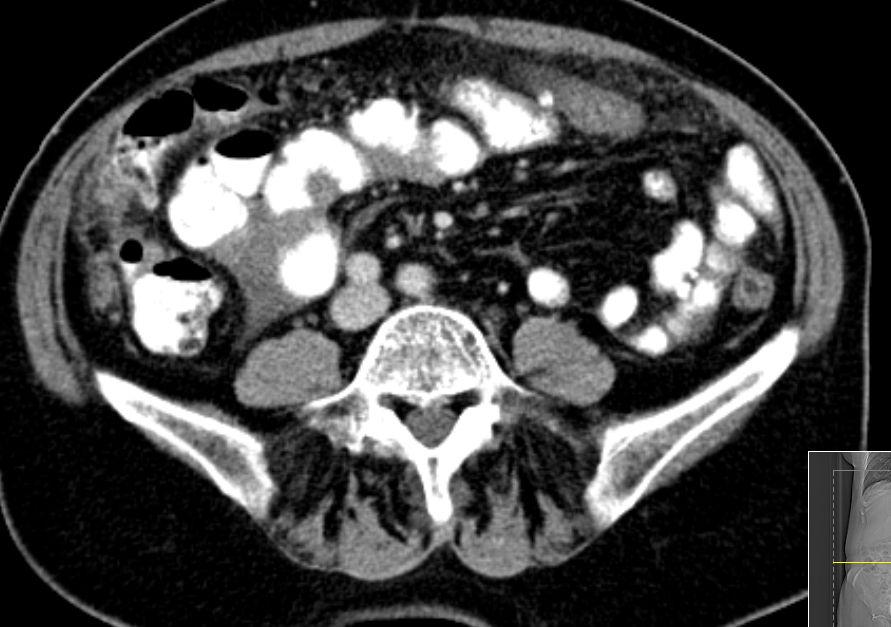

72-jährige Frau mit Peritonealkarziose nach HE mit

Adnexen vor 16 Jahren.

Histologie: Low-grade-serös-papilläres Karzinom

Intraoperatv ausgedehnte Karzinose der Darmserosa und des

Mesenteriums.